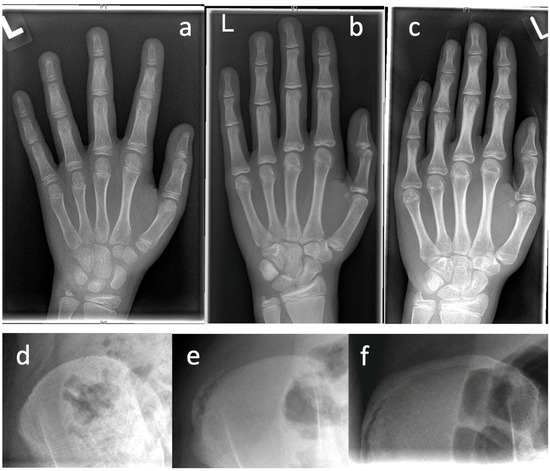

Table 2 presents diagnostic features that can be obtained in patient’s history, clinical examination, and in imaging procedures. Prior to initiation of therapy, determination of skeletal growth potential based on radiologically imaged skeletal maturity according to Risser and Sanders (Figure 1) etc. is of great importance.

3.4.3. Growth Prognosis

Before initiating surgical therapy, knowledge of the patient’s growth potential is of immense importance, since without possible residual growth, some of the procedures cannot guarantee sufficient improvement of the extent of scoliosis. Spinal growth can be estimated on clinical and radiographic parameters. First, in girls, the onset of menarche is considered the point at which the pubertal growth spurt is complete and the growth tendency has already diminished. In most cases, the spine is fully grown about 2 years after the onset of menarche. In boys, the comparable counterpart is the change of voice. The most widespread radiographic method of determining the growth tendency and thus the ability of the spine to be corrected is based on the degree of ossification of the iliac apophysis according to Risser [22]. The iliac apophysis is divided into 6 stages according to different stages of ossification of the apophysis, which begins at the lateral iliac crest and progresses medially. A more reliable measurement is the Sanders classification (simplified Tanner–Whitehouse III system) using an X-ray of the non-dominant hand [21]. The state of ossification of the epiphyses of the hand and wrist defines the expected skeletal growth in 8 groups: juvenile slow (1), preadolescent slow (2), adolescent rapid (early) (3), adolescent rapid (late) (4), adolescent steady (early) (5), adolescent steady (late) (6), early mature (7), mature (8).

Figure 1. Examples for determination of growth potential according to Sanders of ne non-dominant left (L) hand [21]. (ac) and Risser [22] (df), (a)—Sanders 2, (b)—Sanders 3, (c)—Sanders 5, (d)—Risser 0, (e)—Risser 2, (f)—Risser IV.